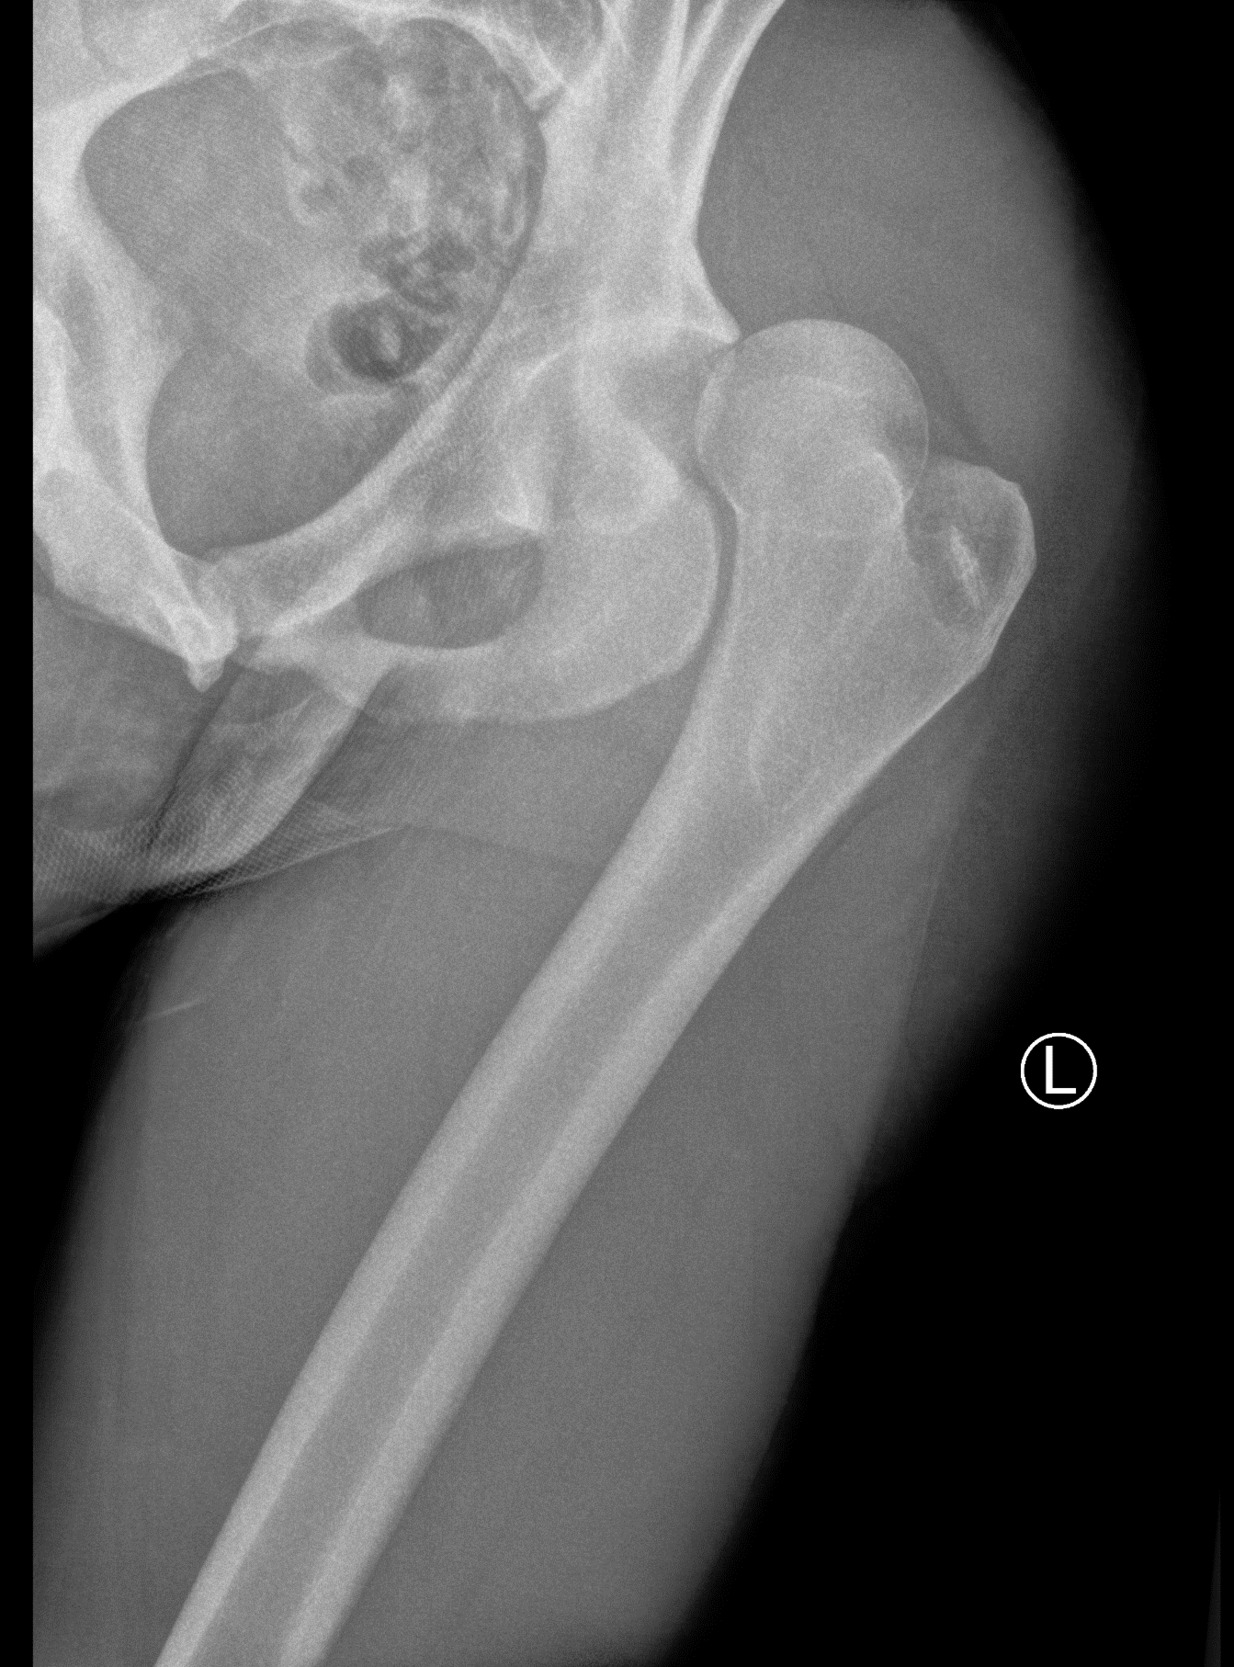

The on-field medical team transported the subject to a nearby emergency room where plain film radiographs revealed a posterior left hip dislocation (Figures 1A-B), negative for fracture, along with mild pre-existing femoral head CAM deformities bilaterally, thus, the diagnosis was consistent with a type 1 dislocation.

The left hip was reduced (Figures 2A-B) and the subject was instructed to be non-weight-bearing on the left lower extremity with bilateral axillary crutches for two weeks, followed by adding 25% weightbearing each week thereafter to weight bearing as tolerated while maintaining standard posterior hip precautions (no hip flexion greater than 90°, no hip adduction, no hip internal rotation) for a total of six weeks. Magnetic resonance imaging was also performed of the left knee and findings indicated a “low grade” left medial collateral ligament sprain.